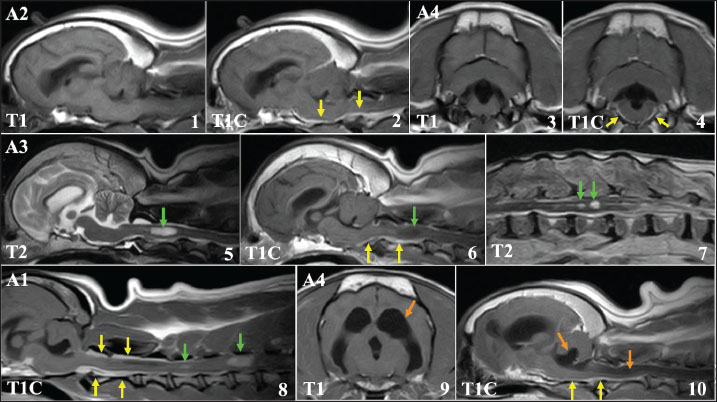

Radiotherapy improved the clinical symptoms of all patients who completed treatment, completing the radiotherapy schedule. In 7 cases with persistent seizure, antiepileptic medication was continued during and after radiotherapy. However, locomotor dysfunctions, such as ataxia and compulsive walking, improved in all 11 cases. MRI examinations performed after the final dose showed regression of primary tumor tissues in all cases (Fig. 2). In 7 cases, tumor tissue completely disappeared on MRI, and in the other 4 cases, showed apparent reductions and in tumor size as measured on MRI images. In all cases, CT evaluations of the thoracic and abdominal cavities performed with the last dose of the radiotherapy showed no distant metastatic lesions. At the end of radiotherapy, all patients were in an acceptable physical condition.

Fig. 2. The effect of radiotherapy on primary brain tumors in FBs. 1, 3: MRI findings before irradiation (contrast-enhanced T1-weighted image). 2, 4: MRI findings immediately after the final fraction of radiotherapy (contrast-enhanced T1-weighted image). Tumor tissue almost disappeared on MRI after radiotherapy.